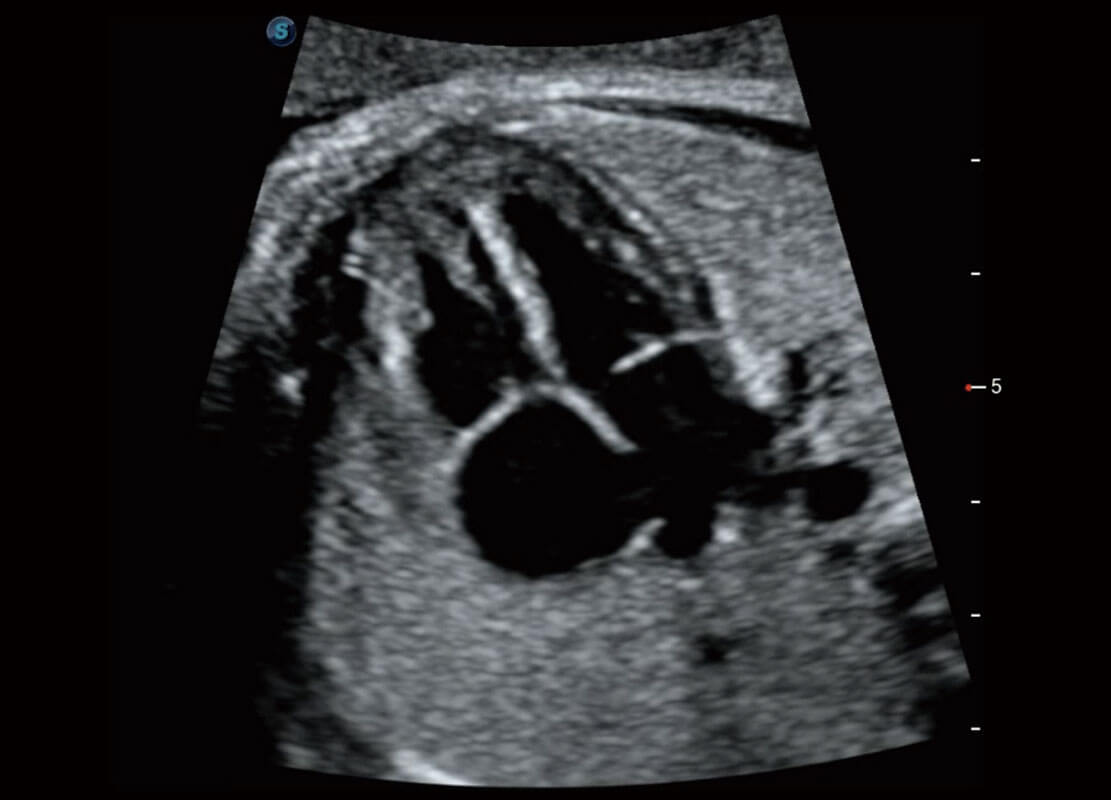

胎心筛查

P60搭载一系列胎儿心脏成像技术,实现更精细的胎儿心脏评估。

• 四腔切面

• 四腔心血流

• 右室双出口

• 胎心容积成像